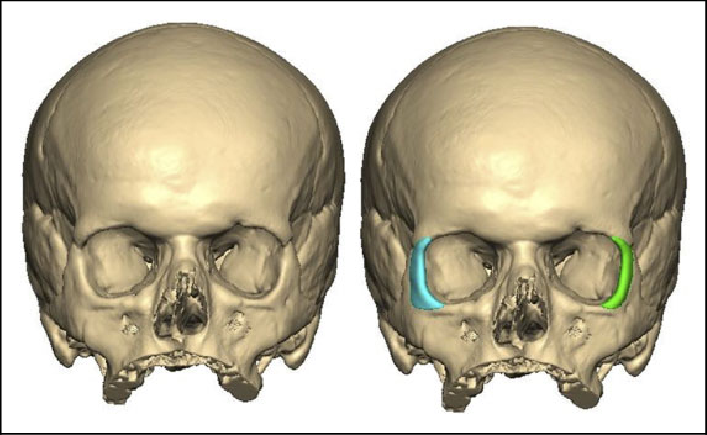

TC de Órbitas com Reconstrução 3D

Técnica útil para avaliação de fraturas complexas e planejamento cirúrgico. Requer aquisição com cortes finos e reconstruções especiais.

Protocolo Recomendado:

- Aquisição isotrópica (0.5-0.6 mm)

- kV reduzido (100-110) para minimizar dose no cristalino

- Reconstruções em MPR (Multiplanar Reconstruction) e 3D

- Algoritmo de alta resolução para avaliação óssea